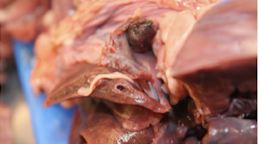

What is occuring in this picture? Is it a post mortem or antimortem change? Why?

This is rumen mucosal sloughing, this is an postmortem change and as you can see in the image their are no signs of hemorrhage or inflammation so this has occured after death.

Common post mortem change that gets misinterpreted as lesion is rumen mucosal sloughing. Lining peels off easily. Tissue reaction not present= post mortem change.